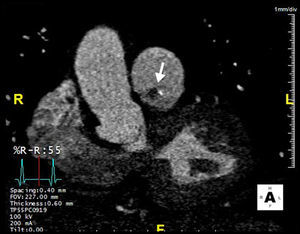

A 42-year-old man with a history of hypertension, type 2 diabetes mellitus and obesity was referred to our center due to the incidental finding of a mass adjacent to the pulmonary valve on a routine transthoracic echocardiogram (Figure 1). He was asymptomatic and physical examination and laboratory values were unremarkable. The transesophageal echocardiogram (Figure 2) revealed a pedunculated, highly mobile hyperechogenic mass, measuring 8 mm × 7 mm, attached to the right pulmonary valve leaflet. The pulmonary valve was functionally normal, with no observed pulmonary regurgitation or stenosis, and no masses were visualized on any other valves or heart chambers. Computed tomography angiography excluded significant coronary stenosis and confirmed the presence of a mass at the level of the pulmonary valve (Figure 3). We concluded that it most likely represented a papillary fibroelastoma. Surgical excision of the mass was decided upon due to its mobility and location, resulting in high risk for embolization. It was successfully resected, with preservation of the valve apparatus. Histopathological examination confirmed the diagnosis of papillary fibroelastoma (Figure 4).